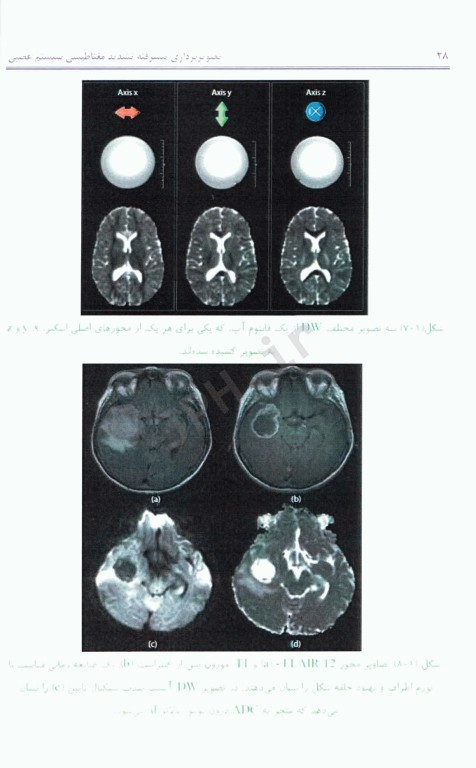

کتاب تصویربرداری پیشرفته تشدید مغناطیسی سیستم عصبی از مبانی نظری تا کاربردهای بالینی تالیف یوآنیس تسوگوس ترجمه دکتر مسعود جباری توسط انتشارات آناطب به چاپ رسیده بر اصول اولیه و تئوری فیزیکی تکنیک‌های پیشرفته تصویربرداری سیستم عصبی با روش تشدید مغناطیسی تمرکز دارد و کاربردهای بالینی این روش‌ها را بیان می‌کند. همچنین مشکلات و آرتیفکت‌هایی که در استفاده از این روش‌ها وجود دارد تاکید می‌کند.

این کتاب در نه فصل تنظیم شده است چهار فصل اول کتاب اصول اولیه تکنیک‌های مورد بحث را توصیف می‌کند و یک دید کلی از هر کدام از این روش‌ها به صورت گام به گام بیان می‌نماید در انتهای هر فصل، مختصری از کاربردهای بالینی هر روش بیان شده است. در ادامه هر کدام از این تیفکت‌های آن روش و استراتژدی‌های کاهش آن بیان شده است. در فصل آخر نیز روش‌های چند پارامتری که از ترکیب این تکنیک‌های پیشرفته حاصل می‌شود توضیح داده شده است.